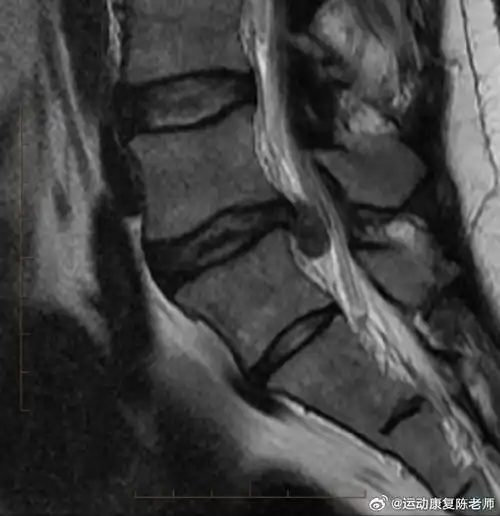

拖→→腰间盘膨出 2.再拖→→腰间盘突出 3.还拖→腰间盘脱出 4.

腰间盘突出,膨出,脱出怎么区分?

什么是腰间盘膨出,突出,脱出?

腰椎间盘突出#一篇文章,带你分清什么是腰椎间盘膨出,突出和脱痴忖